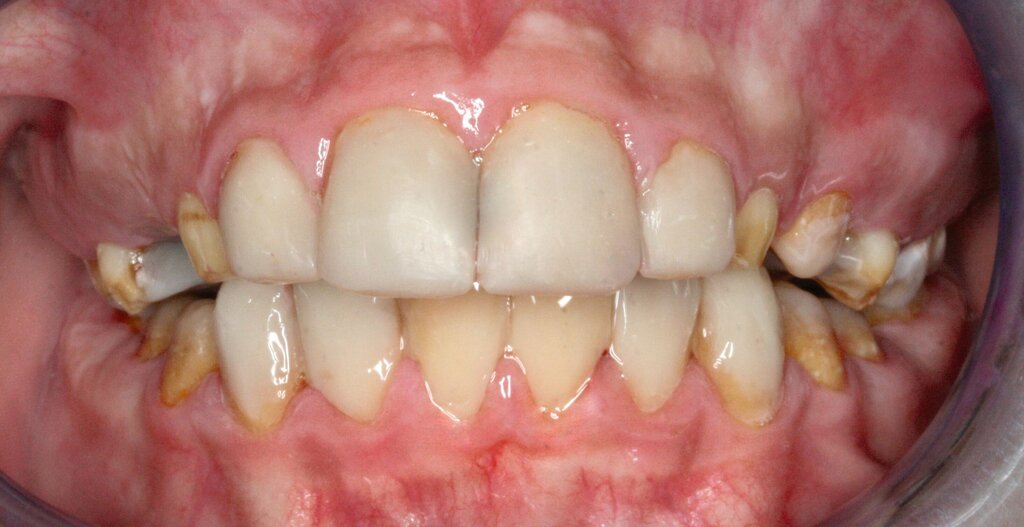

Klinisch zeigten sich ein nicht-kariöses Wechselgebiss mit generalisierter Schmelzhypoplasie an allen Zähnen sowie eine insuffiziente Mundhygiene. Zusätzlich bestanden eine fehlende Mittellinienübereinstimmung, ein Overbite von minus vier Millimetern und ein Overjet von sechs Millimetern (Abbildung 5), die sich phonetisch in einem interdentalen Sigmatismus äußerten. Röntgenologisch waren alle Zähne angelegt, jedoch war der Zahnschmelz stark reduziert oder vollständig fehlend (Abbildung 6).

Die restaurative Versorgung erfolgte in zwei Phasen: Die Frontzähne wurden im Jahr 2018 (Abbildungen 7 und 8), die Seitenzähne im Jahr 2023 behandelt (Abbildungen 9 bis 12). Im Jahr 2018 fiel die Therapieentscheidung auf indirekte Restaurationen, da eine mangelnde Adhärenz des Patienten vorlag, die sich in geringer Geduld für längere Sitzungen äußerte. Zudem war über einen längeren Zeitraum keine zuverlässige Trockenlegung möglich. Durch diese Vorgehensweise konnten die Anzahl und die Dauer der Behandlungstermine reduziert werden.

Die Therapie begann mit einer PZR und der Anfertigung eines diagnostischen Wax-ups auf Situationsmodellen. Dieses wurde in PMMA (PalaVeneer Dentine, Kulzer) umgesetzt. Nach Reinigung der Frontzähne mit Bürstchen und fluoridfreier Polierpaste erfolgte die Anprobe der Kronen. Anschließend wurden die Kronen nach Konditionierung (Clearfil SE Bond, Kuraray Dental) mit einem Befestigungskomposit (Variolink Esthetic DC, Ivoclar Vivadent) unter relativer Trockenlegung mittels Watterollen, Speichelschnecke und Sauger definitiv eingegliedert.